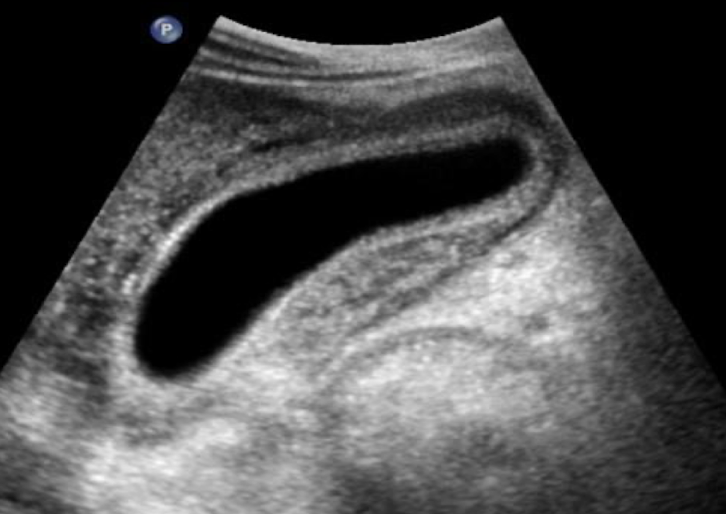

SONO: acute cholecystitis

+ Murphy’s sign

irregular wall > 3 mm

gallstones usually present

wall edema

hyperemia due to inflammation

pericholecystic fluid may be present

??

acute cholecystitis

thickened GB wall

pericholecystic fluid in anterior GB

?FF in posterior GB